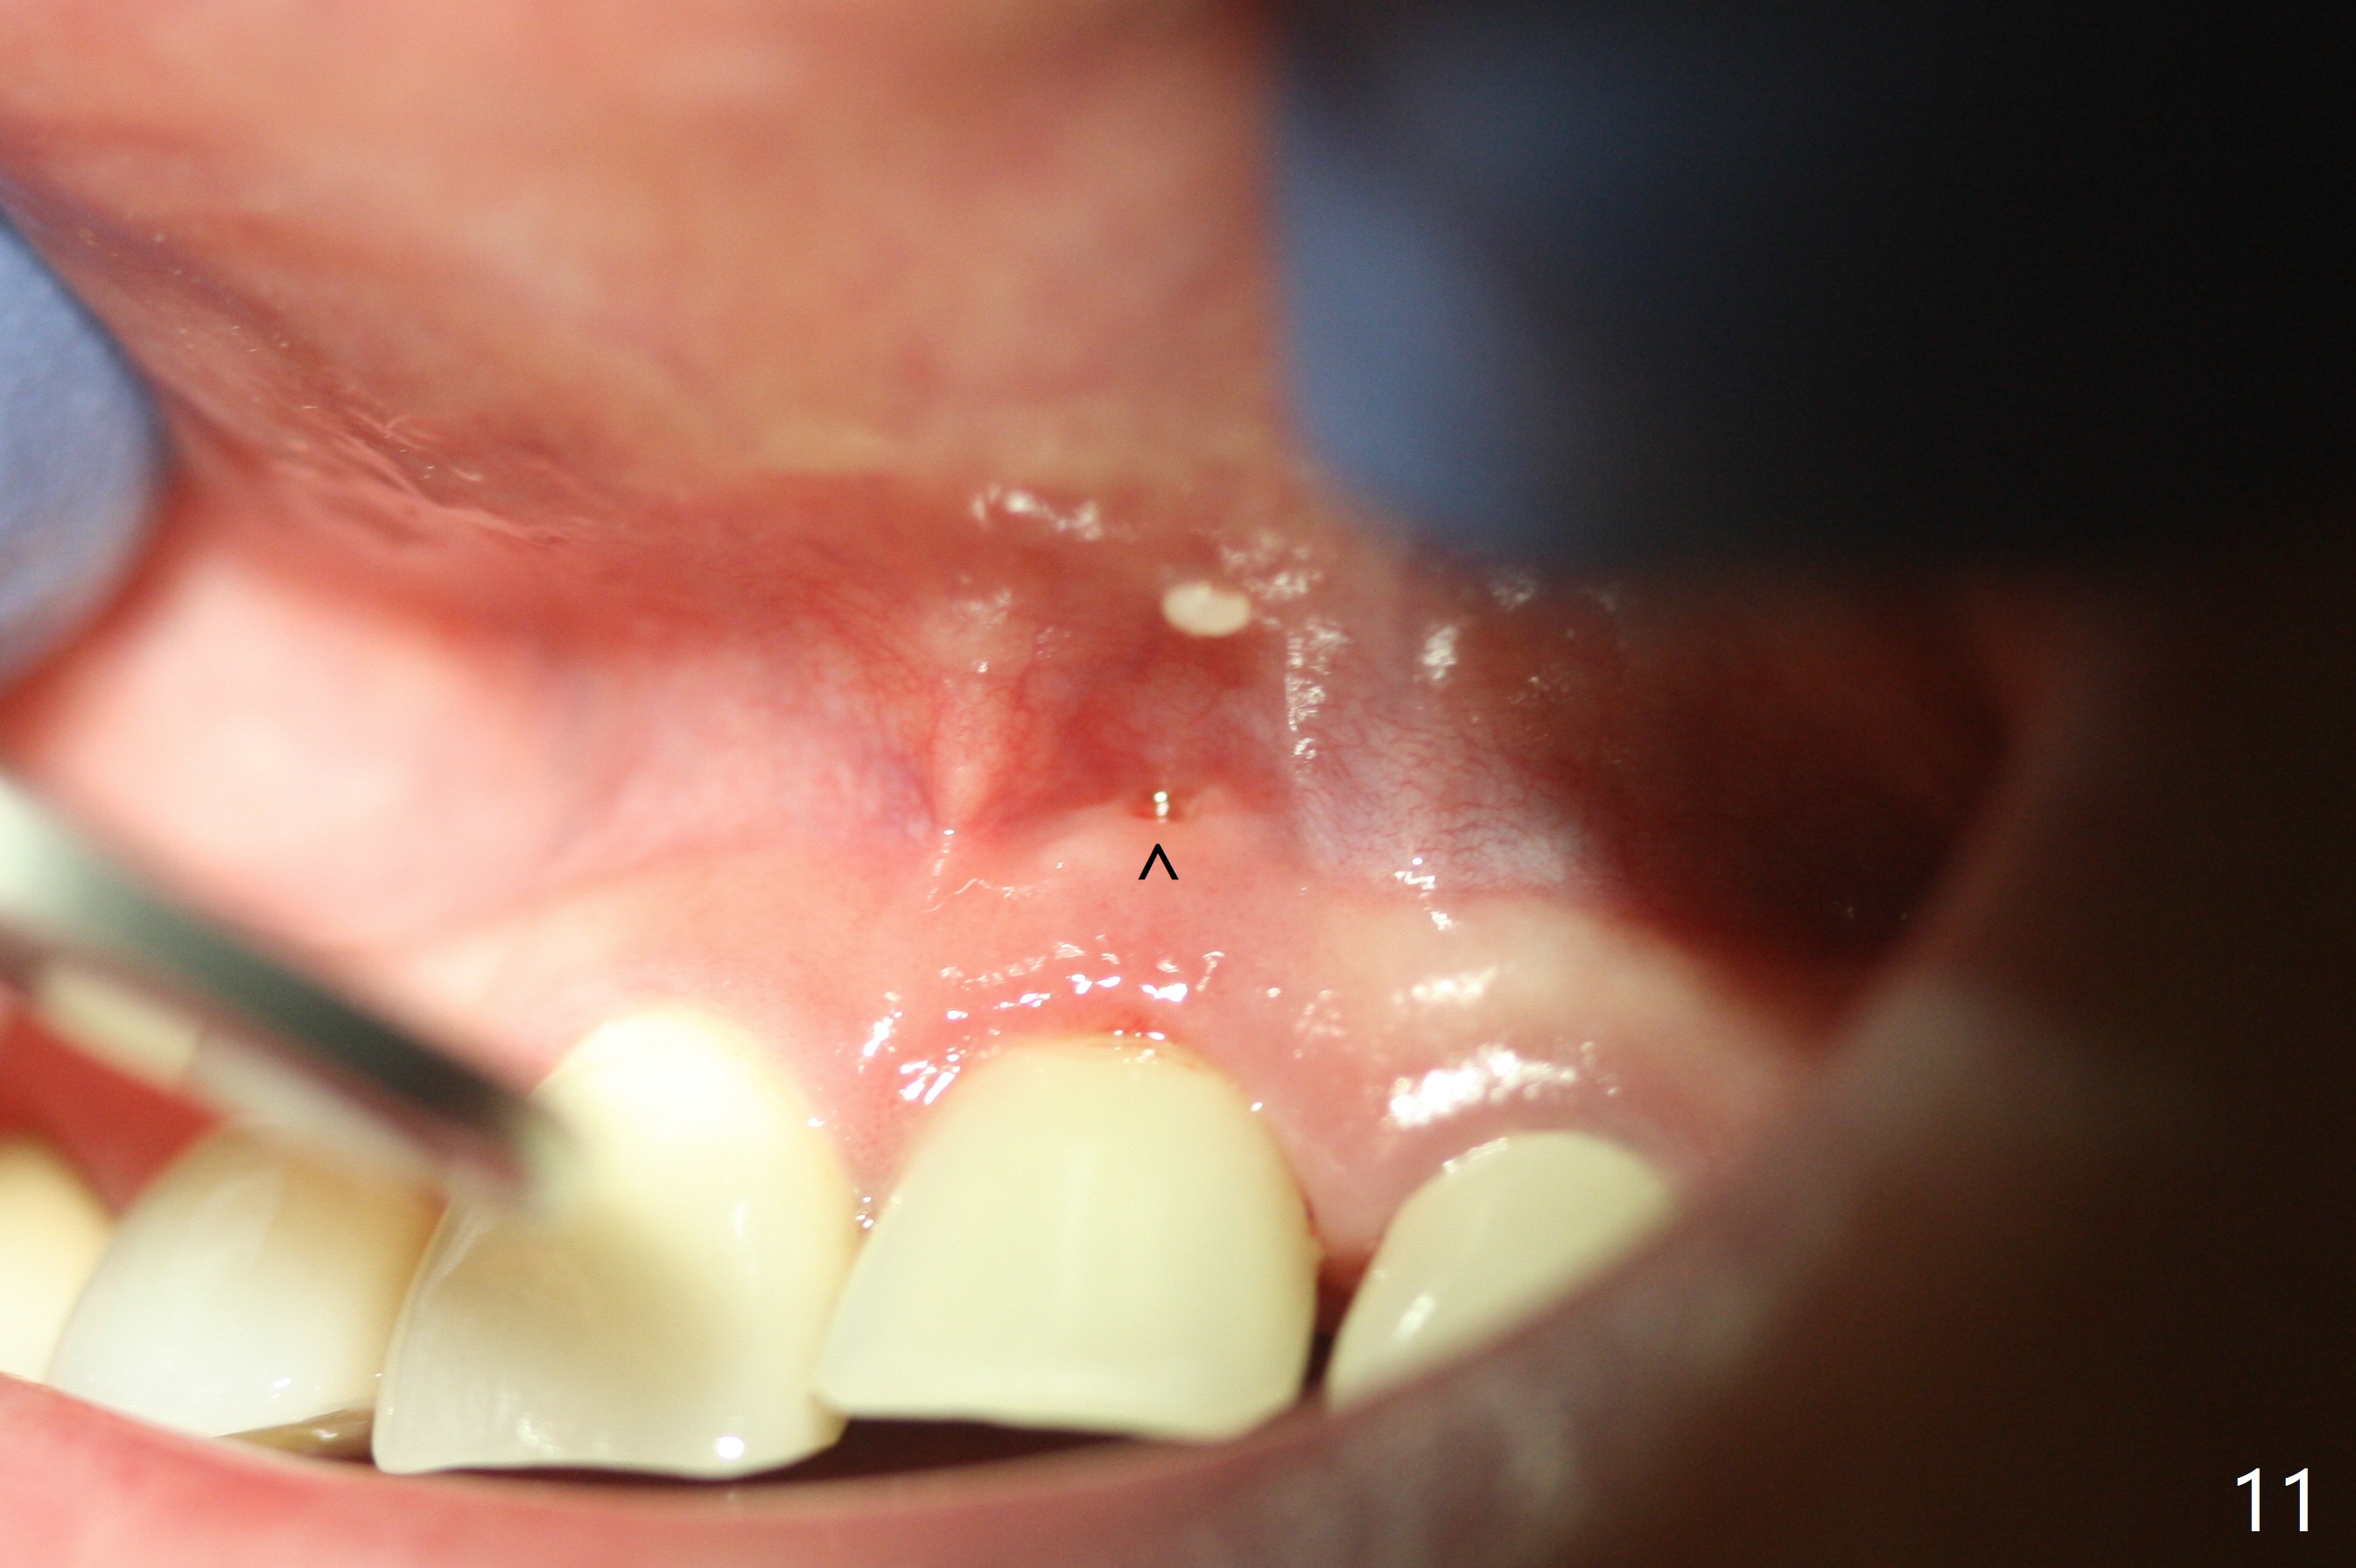

Nasal Floor

The buccal contour at #9 seems to be slightly concave preop (Fig.1,2 (*)). In fact the buccal plate is found to be lost when the tooth is extracted. Osteotomy is initiated as palatal as possible apical, but the occlusion dictates the coronal end of the osteotomy should be buccal, leaving the buccal gap ~ 2 mm for bone graft. The initial osteotomy (18 mm deep) appears to be close to the Incisive Foramen (Fig.3 blue dashed line). The nasal floor appears to be intact when the drill is removed. Subsequent osteotomy is adjusted so that the apical end of the osteotomy moves distal; when a 3.8x15 mm dummy implant is partially placed, there is clearance (Fig.4). It remains so when a definitive implant is seated (Fig.5); Vanilla graft is placed (Fig.5 *) before placement of a 4.5x5.5(3) mm abutment. More allograft is placed when an immediate provisional is fabricated (Fig.6 arrow and *). The gingiva remains to be recessive 1 month postop (Fig.7). It seems to be related to the bulky gingival margin of the provisional (Fig.8 *). After trimming the latter (Fig.9 *), the gingival margin immediately returns close to normal (Fig.10). The gingival margin is even between #8 and 9 two months postop, but the bone graft is exposed apically (Fig.11 ^). It may heals by itself. Otherwise debridement, regraft, PRF and suture are pending. The coronal portion of the socket heals 4 months postop (Fig.12). The gingival cuff forms by the immediate provisional (which is removed for impression) 4 months postop (Fig.13 *). While the full Zirconia crown at #7 remains intact (Fig.14), the PFM at #9 has porcelain chip (Fig.15). It is partially due to the occlusion; while the crown at #7 has clearance with the opposing dentition (Fig.16 *), the one at #9 has no. The access hole at #9 (Fig.17 *) seems to weaken the crown structure. There is no access hole at #7. No solid posterior support is another contributing factor for chip (Fig.18). The buccal plate has mild atrophy at #7 and 9 (Fig.19 *). A piece of bone graft is being expelled apically at #9 (Fig.20 >) and is removed subsequently (Fig.21). Before impression for repacking porcelain, the opposing incisal edge has been shortened (Fig.22 arrows, as compared to Fig.16). Since the ideal access hole is at the incisal edge (Fig.25 black circle), buccal to the existing one (Fig.24 A), the abutment is torqued before the repaired crown is recemented (Fig.23). Finally the crown has occlusal clearance (Fig.26). Porcelain chips again around the access hole of PFM 1.5 years post 2nd cementation. The dense bone at the crest (*) cannot explain why the abutment is not loose, since it remains incompletely seated (>). As it was trimmed short, an angled abutment is used (Fig.28). The coronal end is lingual, while #9/24 is edge to edge. The lingual aspect of the coronal end of the abutment is heavily trimmed to reduce bulkiness. To prevent chip, Zirconium crown will be fabricated in spite of the fact that it does not match the PFM of #8 (potential shade discrepancy). The patient is pleased with the new Zirconia crown (Fig.29).